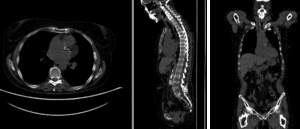

rigidrigid

affine alignmentaffine alignment

BSpline registration of full volumes. 9 x 9 x 5 gridBSpline registration of full volumes. 9 x 9 x 5 grid

BSpline registration of full volumes. 11 x 11 x 7 gridBSpline registration of full volumes. 11 x 11 x 7 grid